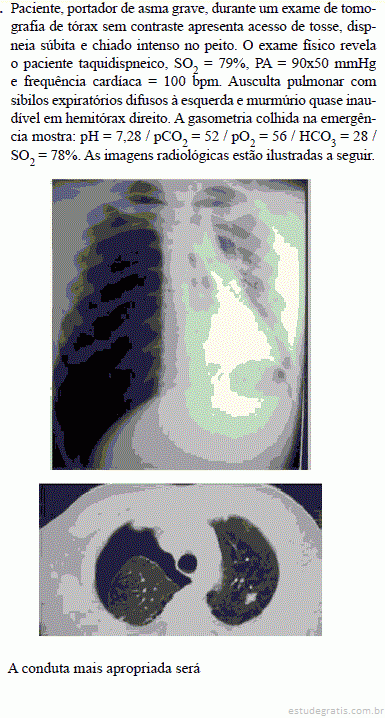

A. coloc...